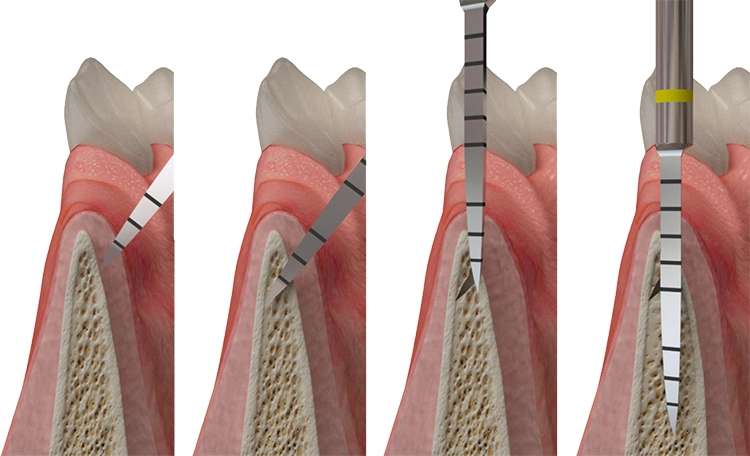

Im „weichen“ Knochen (D3+D4) erfolgt die Pilotbohrung lediglich mit den ersten beiden konischen Dreikantbohrern und bereitet das Implantatbett weiter ausschließlich mit den CHAMPIONS Condensern auf. Condenser sind Knochen verdichtende Instrumente in den Durchmessern 2,4 / 2,8 / 3,0 / 3,3 / 3,8 / 4,3 / 4,8 / 5,3 mm (Abb. 17).

Erreicht man z. B. „handfest“ (etwa 20 Ncm) mit einem Condenser ø 3,3 mm eine Stabilität, so inseriert man ein Implantat ø 3,5 mm. Würde man die Stabilität erst mit dem Condenser ø 5,3 mm erreichen, so würde ein (R)Evolution Implantat gleicher Länge mit Durchmesser 5,5 mm eingesetzt werden.